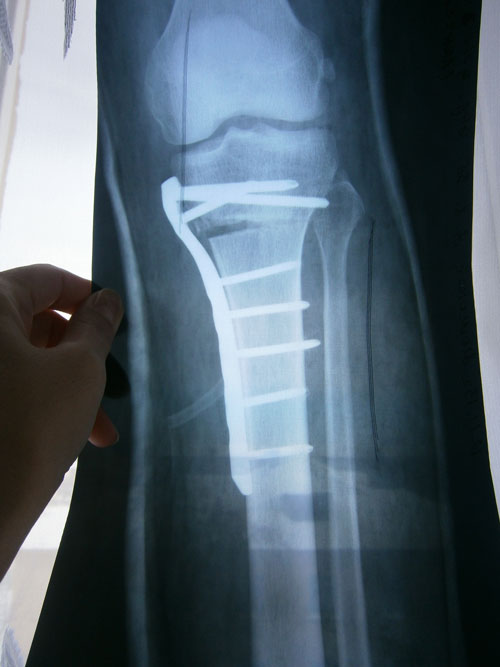

Здравствуйте! Хочу узнать исправляете ли вы неудачные результаты после коррекции? У меня была операция в ноябре 2013 года с применением пластины (неполный перелом) на правой ноге, в декабре 2014 я удалила пластину, результатом не довольна, особых изменений нет. Сколько сейчас стоит операция? Какие условия для иногородних? Я из Омска.Прилагаю фото : первое до операции, рентген после операции, ну и сам результат. Заранее спасибо.

Здравствуйте, Ася! Исходник (до операции) отличный! Надколенники расположены по центру, истинная о - образная кривизна, стройная, рослая, ножки - палочки! Мечта хирурга!

Результат будет красивым, ножки ровными (ортопедическую ось исправим).